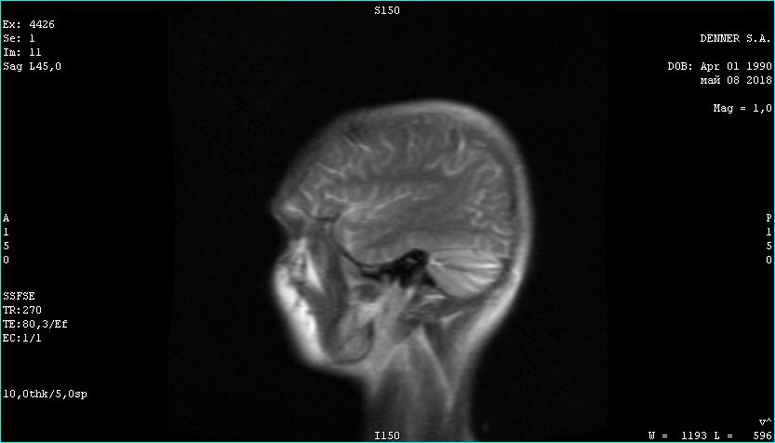

Вверху февраль 2018. Внизу май 2018

Тип файла: jpg 08.05.2018 г.jpg (24.0 Кб, 693 просмотров)

Опухоль контраст не накапливает. Связи с костью уже не имеет. Головка опухоли начала разлагаться. Врачи в шоке. А я злорадствую. Сергей мне поверил и сейчас копает огород на Алтае, хотя должен был умереть в июле. Моя карма получила жирный плюс...

Фото мрт сделаны немного в разных ракурсах, (зачем, непонятно-наверное чтобы не признавать эффект оздоровления ), но положительная динамика все равно видна. И пациент начал жить полноценной жизнью - секс, загар, копание огородов и рыбалка...